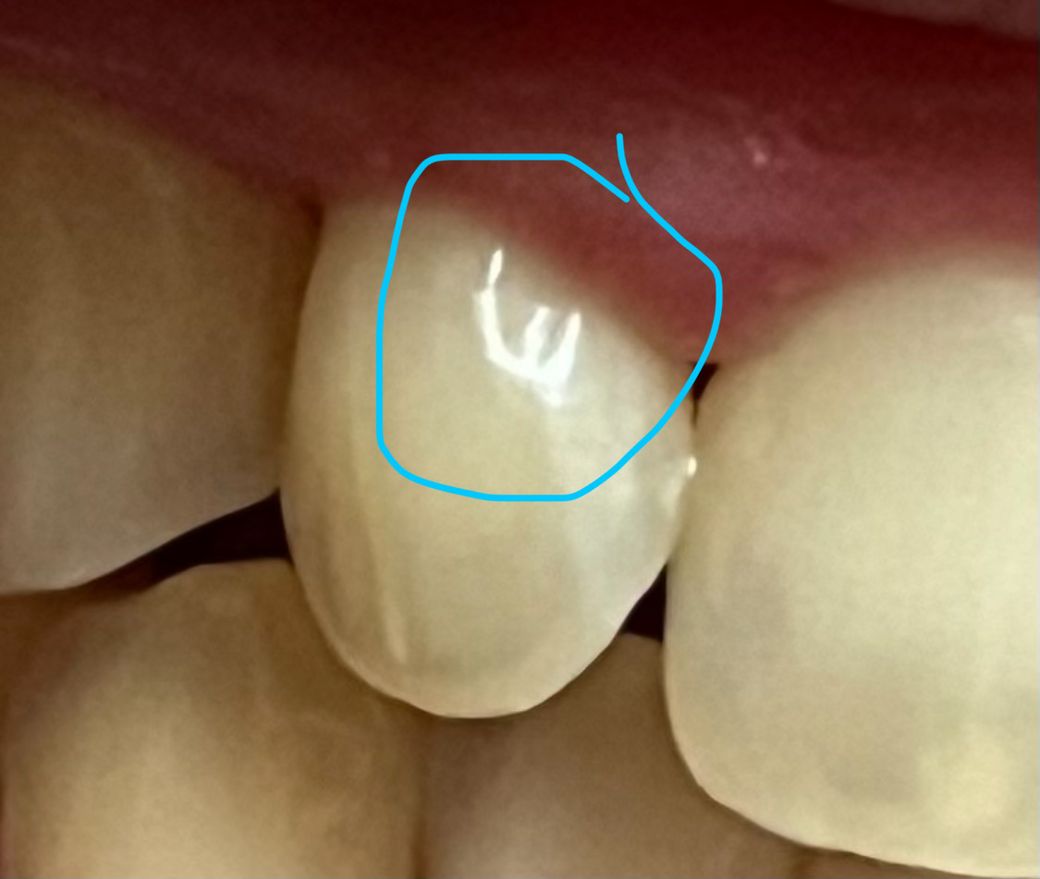

그런데 거울을 보니 제가 긁었던 이중 하나가 잇몸 아래로 0.1mm깊이 정도에 길이 1mm정도가 패인것 처럼 보여서요..

사진 첨부합니다.

패인 부분은 그대로인거같아서 사진 첨부합니다

사진상 보이는 패여있는 흔적은 철로 긁어서 만들 수 있는건 아닌 것 같습니다 물론 철로 안긁는게 좋고요, 원래부터 그런 흔적이 있었을것 같습니다

현재 쇠로 긁어서 파였다기보다는 치경부에 마모가 된 것으로 보입니다. 이 경우에는 치경부 마모 부위를 레진으로 메꾸는 치료가 가능하며,만약 시리거나 통증 불편감이 발생시 치과 에서 치료를 받길 권합니다.